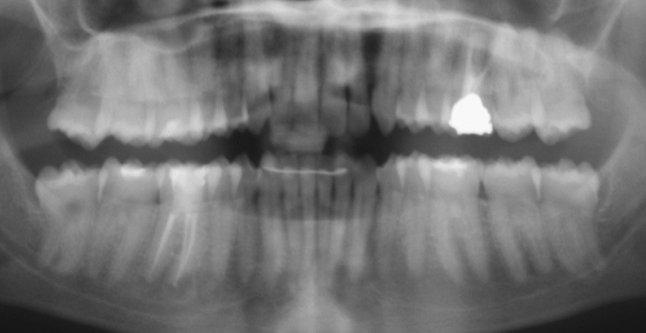

العصب السنخيalveolar nerve يكون احيانا في وضع قريب جدا من ذروة جذور اضراس العقل

الاضراس السفلية تكون في بعض الاحيان قيبة جدا ومتداخل مع قناة العصب السنخي

قدر هذه المريضة ان اضراس العقل السفلية قريبة جدا من مجرى العصب السنخي